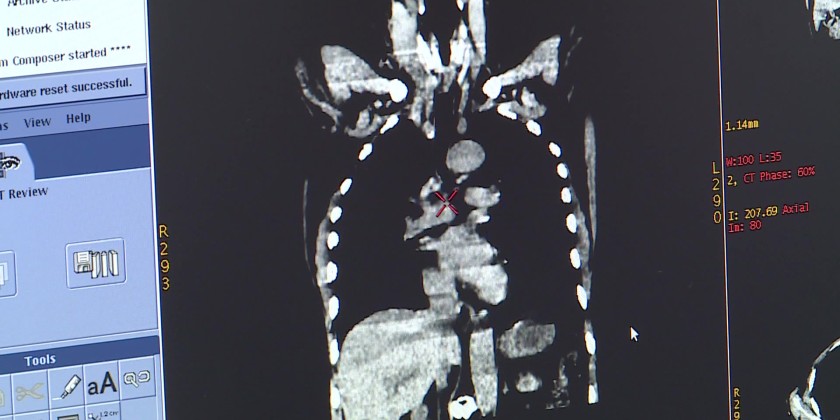

The new synchronized system enhances the precision and effectiveness of high-tech radiotherapy, minimizing side effects and reducing complications. Particularly for tumours located in organs that move with respiration, such as the lungs and liver, the 4D simulation provides real-time imaging to ensure more accurate treatment planning and dosage calculation tailored to each patient.